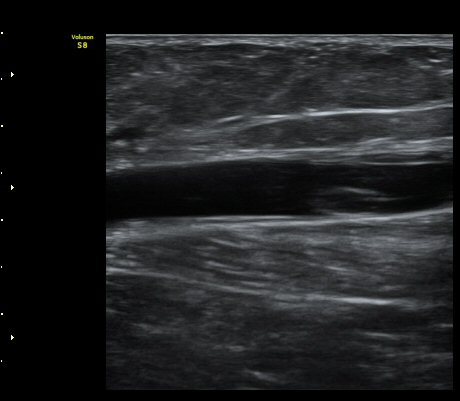

¹«¸ ¾Æ·¡ ÀåµýÁö Á¾´Ü¸é°Ë»ç¿¡¼ ÇÇÇÏ ¿¬ºÎÁ¶Á÷°ú ºñº¹±Ù »çÀÌ¿¡ ¼ö¾×Àú·ù(º£ÀÌÄ¿¾¾ ³¶Á¾ÀÌ ÅÍÁ®¼ Èê·¯³ª¿Â)°¡ °üÂûµÈ´Ù(»çÁø 4).

¹«¸ ¾Æ·¡ ÀåµýÁö Ⱦ´Ü¸é°Ë»ç¿¡¼ ÇÇÇÏ ¿¬ºÎÁ¶Á÷°ú ºñº¹±Ù »çÀÌ¿¡ ¼ö¾×Àú·ù(º£ÀÌÄ¿¾¾ ³¶Á¾ÀÌ ÅÍÁ®¼ Èê·¯³ª¿Â)°¡ °üÂûµÈ´Ù(»çÁø 5).